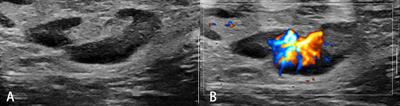

in Cancer Imaging and Image-directed Interventions